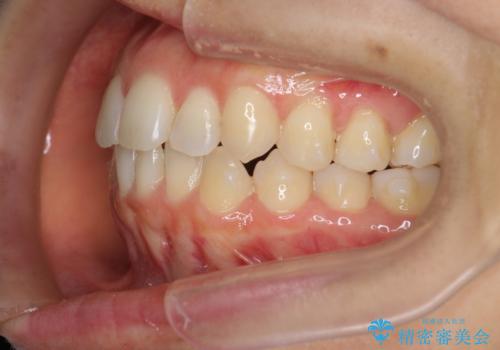

前歯のがたつきをしっかり治すマウスピース矯正

- 前歯のガタガタをきれいに並べたい、と希望され来院されました。

がたつきのないきれいな歯並びに仕上げることができ、満足いただくことができました。